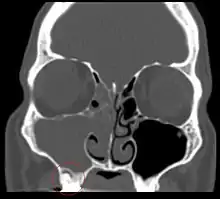

Sinusitis is inflammation of the paranasal air sinuses. Odontogenic sinusitis is an inflammatory condition of the paranasal sinuses that is the result of dental pathology, most often resulting from prior dentoalveolar procedures, infections of maxillary dentition, or maxillary dental trauma.[5] Infections associated with teeth may be responsible for approximately 20% of cases of maxillary sinusitis.[6] The cause of this situation is usually a periapical or periodontal infection of a maxillary posterior tooth, where the inflammatory exudate has eroded through the bone superiorly to drain into the maxillary sinus. Medical management and treatment of the underlying dental pathology remains a critical initial step in the treatment of odontogenic sinusitis, however recent literature suggests that a significant portion of patients may require endoscopic sinus surgery for successful disease resolution.[5] Once an odontogenic infection involves the maxillary sinus, it is possible that it may then spread to the orbit or to the ethmoid sinus.[6]